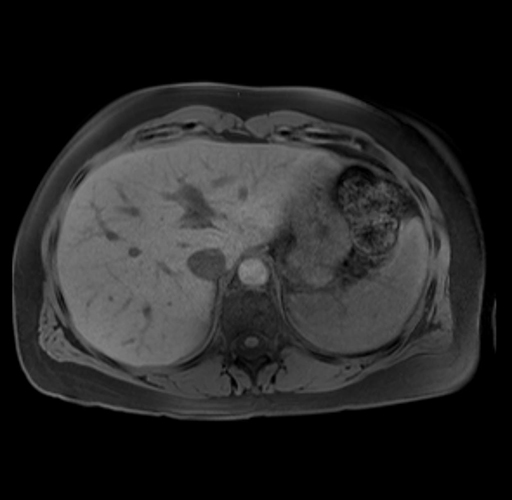

Imaging Analysis

Look through the patient's CT scan to identify any areas of concern for the necessary procedure.

Based on your CT findings, which issue(s) are present and would give reason for "planned slowing down moment(s)" in this case?